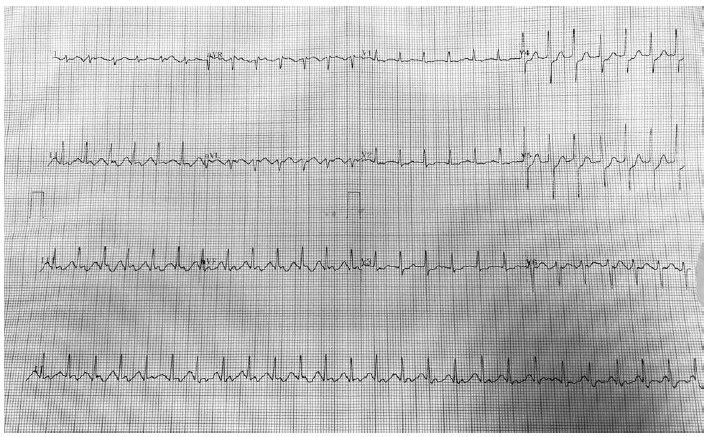

Paciente do sexo masculino, 60 anos, hipertenso, admitido para cirurgia de osteossíntese de fratura de rádio distal esquerdo. Foi realizado bloqueio de plexo braquial com 20 mL de lidocaína a 2% com vasoconstrictor, sob ansiólise. Durante a injeção do anestésico, o paciente relata sensação de “batedeira no peito”, mas sem outros sinais ou sintomas. O monitor mostra FC de 150 bpm, PA de 160 x 90, SpO2 95%. Você interrompe a injeção e solicita a enfermagem um eletrocardiograma de 12 derivações, que foi realizado e está ilustrado pela figura:

Diante do quadro apresentado, assinale a opção que exibe o diagnóstico CORRETO: